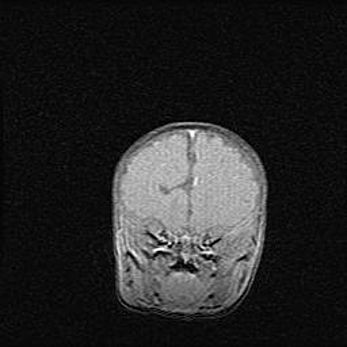

Наружная гидроцефалия с возможной атрофией височных областей.

Возраст: 28 дней

Вес: 3670 г

Пол: мужской

Окружность головы: 38 см

Срок гестации: 40 недель

Гидроцефалия головного мозга у новорожденных – это заболевание, которое характеризуется скоплением избыточного количества спинномозговой жидкости в желудочковой системе головного мозга в результате затруднения её перемещения от места выработки к месту поглощения в кровеносную систему или вследствие нарушения абсорбции. При открытой наружной форме гидроцефалии у новорожденных расширяются и переполняются субарахноидные пространства.

При нормотензивных  формах,  которые,  как  правило,  являются  следствием  перенесенных ишемических  повреждений  паренхимы  мозга,  возможно  сочетание микроцефалии  с нормотензивной гидроцефалией. В основе данных изменений лежит атрофия больших полушарий с преимущественной  локализацией  в  лобно-височных  областях.